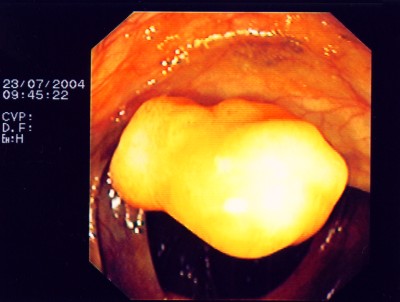

Noch gutartiges Gebilde des Mastdarmes mit schweren Zell- veränderungen. Hier ist eine den Schließmuskel erhaltende Operation möglich - transanale mikroskopische Tumorentfernung (TEM).

Wie bei den Abbildungen 28 und 30 handelt es sich um einen breitbasigen, relativ flachen, noch nicht entarteten Polyp, der sich mit einer Schlinge nicht vollständig abtragen ließe.